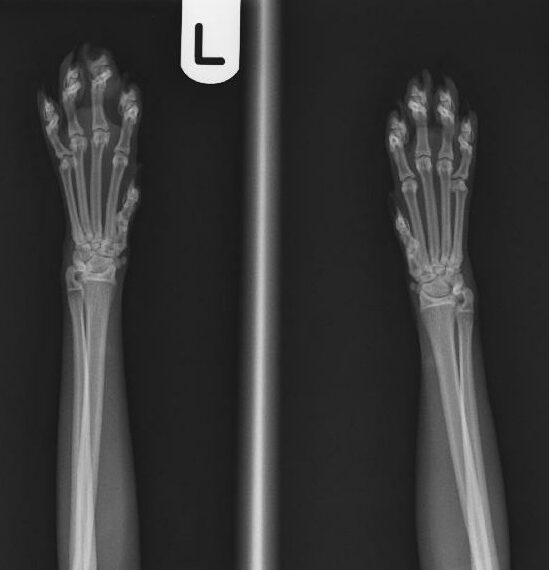

Bij een röntgenfoto wordt er met behulp van röntgenstralingen een opname gemaakt van de binnenkant van het lichaam. Bepaalde weefsels in het lichaam houden de röntgenstralen tegen, terwijl andere ze gemakkelijk doorlaten. Hierdoor is het mogelijk om verschillende structuren in het lichaam op een röntgenfoto te zien.

Röntgenfoto’s kunnen worden gebruikt om verschillende aandoeningen en problemen te helpen diagnosticeren, variërend van botbreuken tot problemen met interne organen zoals de longen, lever en nieren. Ook worden röntgenfoto’s gebruikt voor het maken van officiële HD/ED-röntgenfoto’s voor het beoordelen van de heup- en ellebooggewrichten bij bepaalde hondenrassen.